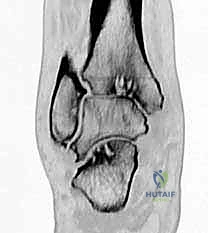

FIG 3 • CT is helpful for detecting subtalar lesions.

We have three sizes of TNK prostheses: small, medium, and large. We meticulously template for the TNK implant directly on the preoperative weight-bearing ankle radiographs. We mark our proposed resection level, aiming for 8 to 15 mm above the distal tibial surface, incorporating a 10-degree posterior slope. The anteroposterior dimension of the tibial plafond is measured to ensure optimal support for the tibial implant. Our goal is always to select the largest possible component that fits the anatomy, maximizing surface contact and biomechanical advantage. In complex cases, especially those with significant deformity or subtalar pathology, we often utilize CT scans and even computer simulation for more precise templating and a detailed understanding of the bony architecture.